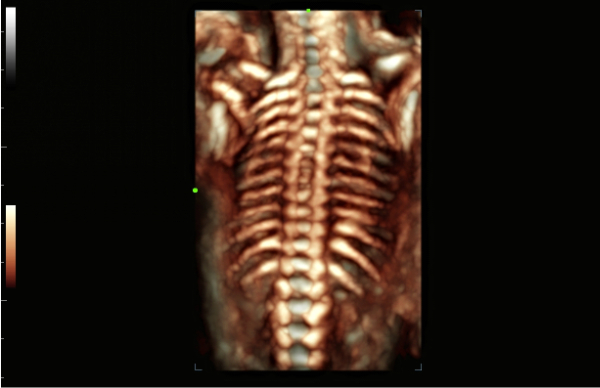

GalerĂa de imĂĄgenes